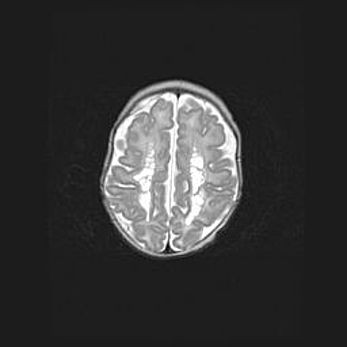

Неполная лизэнцефалия (пахигирия). Открытая гидроцефалия.

Возраст: 17 дней

Вес: 3110 г

Пол: мужской

Окружность головы: 33,5 см

Срок гестации: 35-36 недель

Лизэнцефалия—недоразвитие корковой пластинки и мозговых извилин в результате нарушения миграции нейронов коры. Поверхность мозговых полушарий гладкая. Микроскопически выявляется отсутствие нормальных слоев коры и скопление групп нейронов в подкорковом белом веществе.

Пахигирия—уменьшение числа вторичных извилин. В пораженном полушарии нервные клетки образуют толстый недифференцированный слой с неправильно расположенными нервными волокнами и группами гетеротопных клеток. Нервные клетки незрелые. Белое вещество истончено. При этом нередко аномально развит корково-спинномозговой путь.